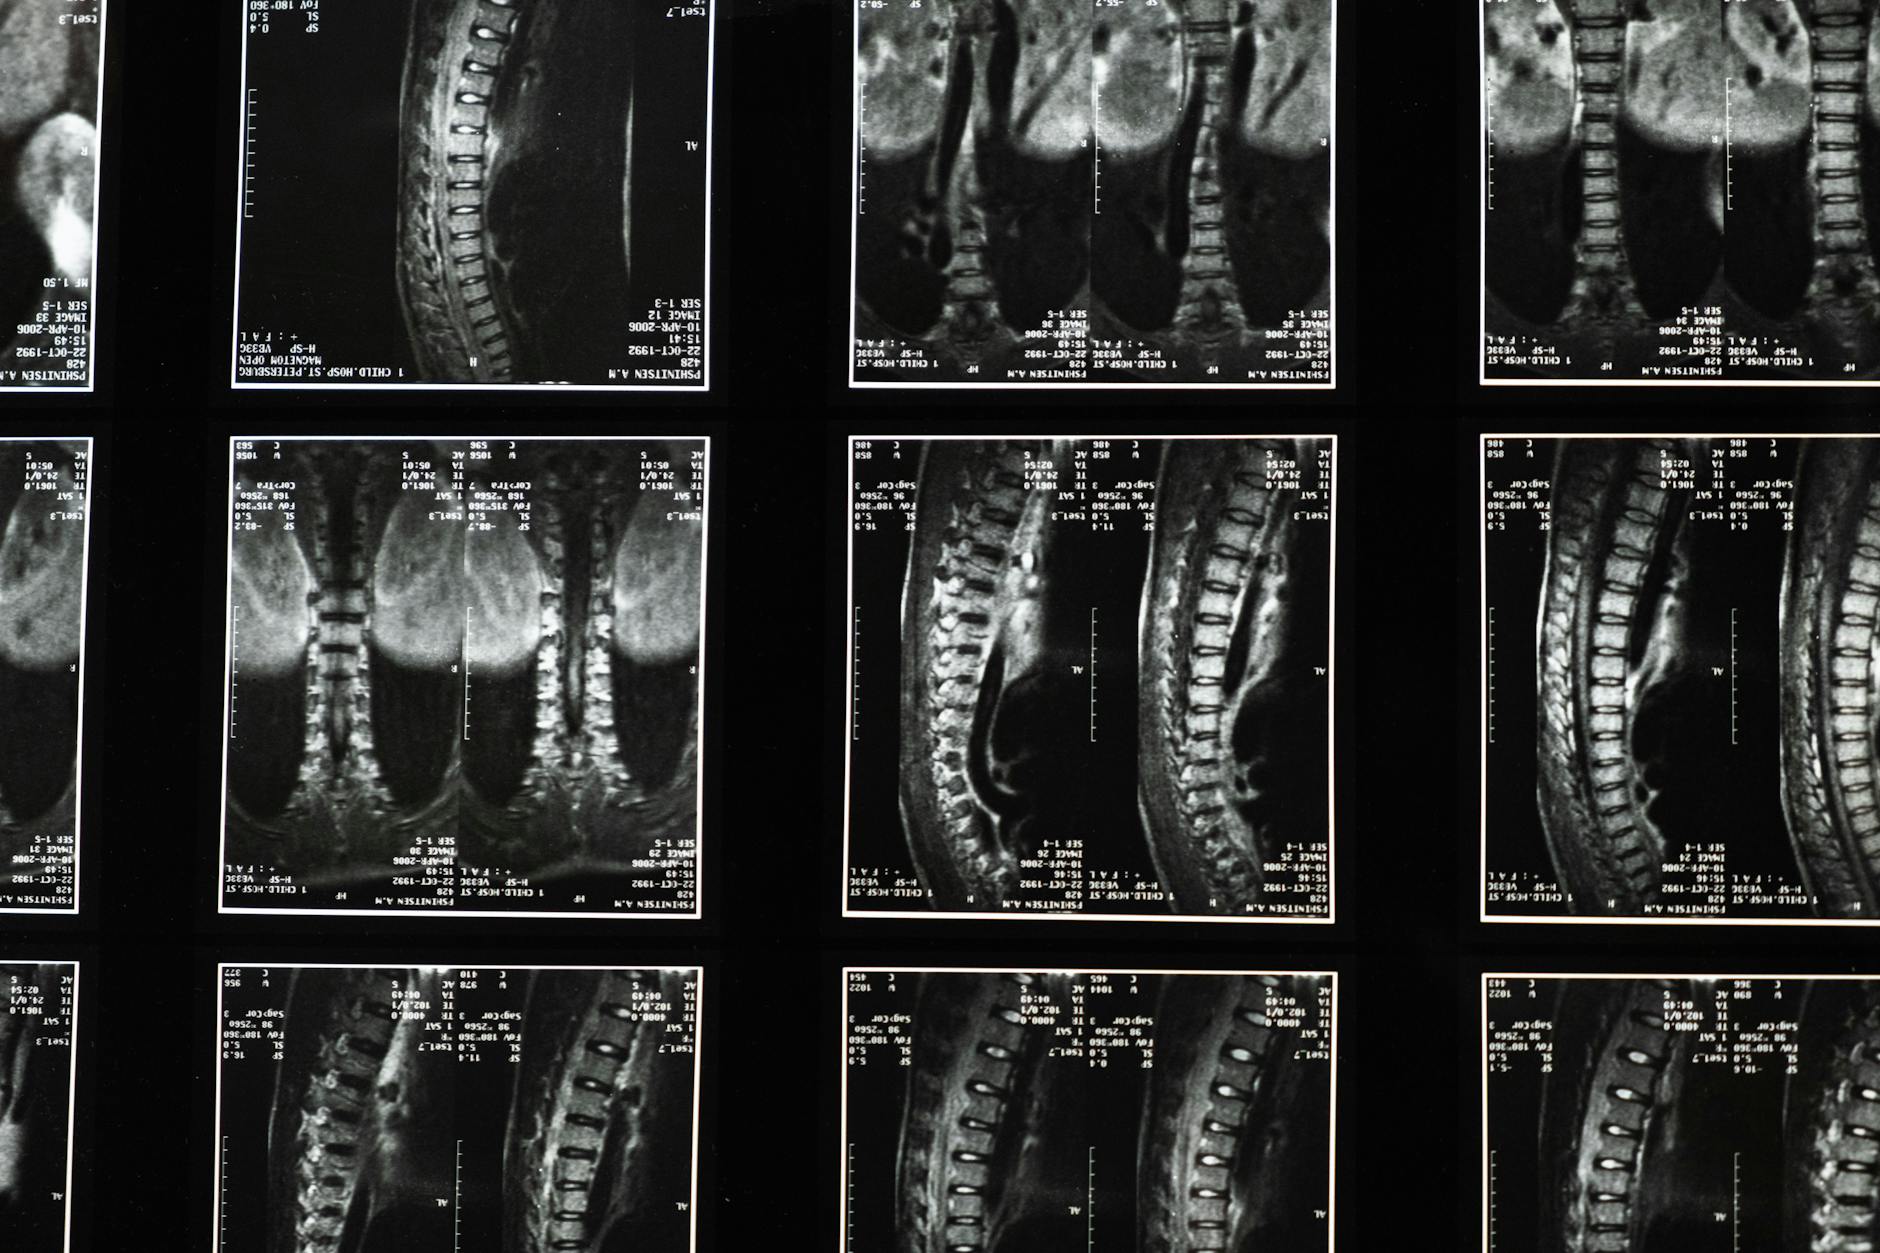

During an evaluation, a clinician will gather a careful history and perform a focused neurologic exam to assess sensation, strength, reflexes, and gait. The clinician will ask about saddle-area symptoms, bladder and bowel changes, and any signs of progression. Depending on findings, imaging—most commonly MRI of the lumbar spine—may be recommended to visualize nerve compression. Blood tests or other studies may be used in specific situations. It is important to recognize the limits of assessment today: a single visit cannot always rule out CES, and decisions are made in collaboration with you, considering symptoms, risks, and preferences.